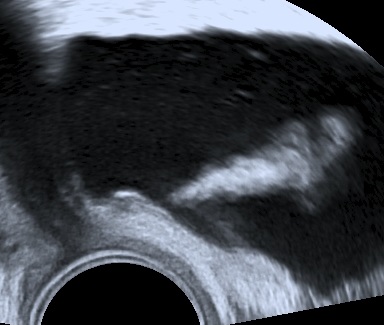

The following images represent an abnormal passageway between the ureter and the vaginal apex following a complicated hysterectomy.